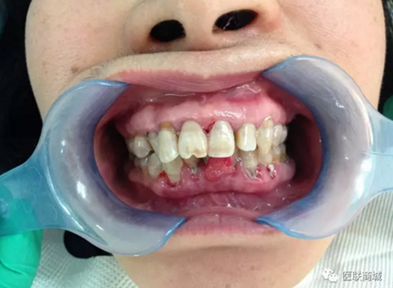

檢查:全口口腔衛(wèi)生差,牙齦紅腫,齦上牙石(+++),齦下牙石(+++),BOP(+),AL為3mm, BI=4,PD大于3mm,下中切牙間唇側可見如花生米樣大小腫物,碰觸出血,有蒂,基底寬,表面可見充血,下前牙松動一度。上下牙列不齊,下前牙間可見間隙。深覆牙合3度。